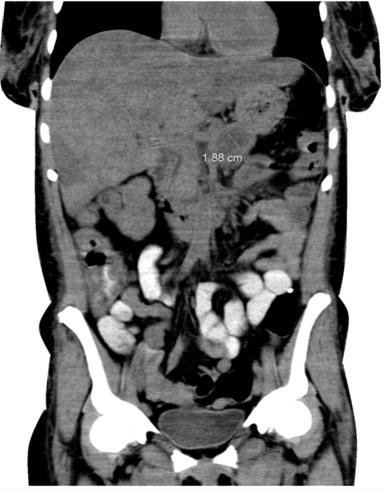

The patient was presumably diagnosed with CMV-induced acute pancreatitis and all her medications temporarily stopped. She was given intravenous (i.v.) fluids, analgesics, doripenem, and a 3-week course of intravenous ganciclovir. One week later, her pancreatitis resolved and she was restarted on trimethoprim-sulfamethoxazole and azithromycin. On hospital day 14, her antiretroviral therapy medications were also resumed. Upper endoscopy was performed which revealed multiple 0.1 to 2 cm firm nodules in the stomach and duodenum. The biopsy specimen was consistent with Kaposi’s sarcoma (Figure 4). Ophthalmology examination revealed bilateral CMV retinitis (right eye more than left eye), with an old branch retinal artery occlusion of the left eye. After 4 weeks of in-patient management, a repeat abdominal CT showed resolved pancreatitis with dilated pancreatic duct (Figure 5). The patient was discharged home without any clinical evidence of recurrent pancreatitis.

Figure 5. CT scan of the abdomen showing the relatively normal pancreas in our patient 3 weeks after resolution of her symptoms. Note the dilated pancreatic duct, a common sequelae of acute pancreatitis. |